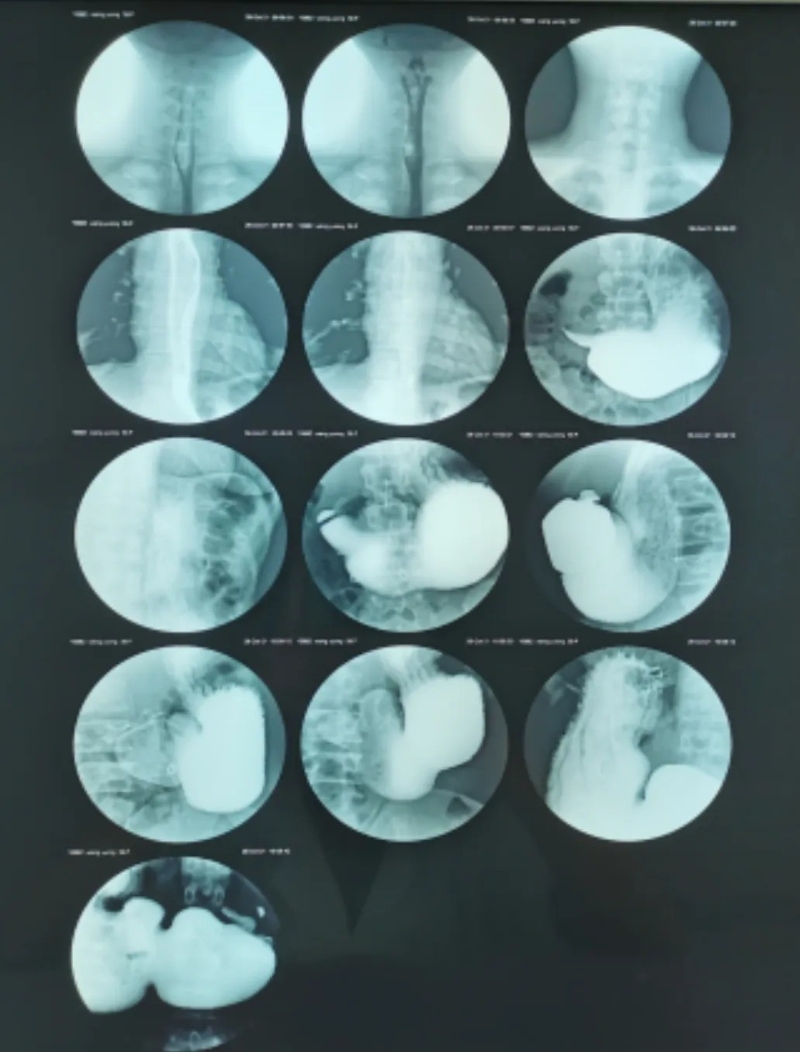

正当我疑惑,上消化道造影结果出来了:胃下垂,慢性胃炎,胃潴留,十二指肠球部欠规整,请结合临床。消化科建议心脏情况好转后,再行胃镜检查。

患者上消化道造影图